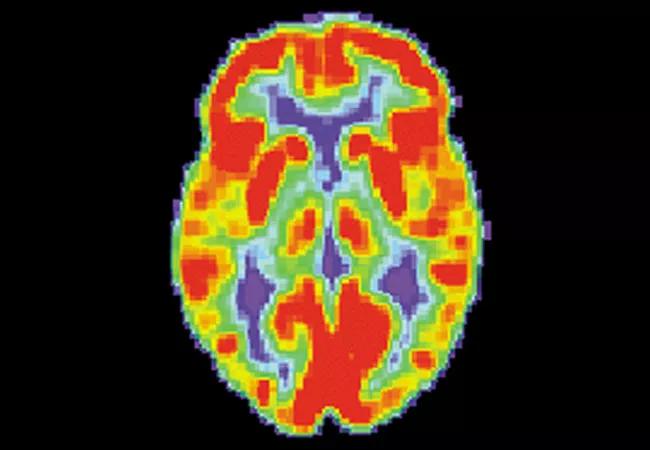

PET Ligand GE-180 Cleared for Testing to Assess Inflammation in Neurodegenerative Disease

Cleveland Clinic Lou Ruvo Center for Brain Health has received FDA approval of its Investigational New Drug (IND) application to test the GE-180 ligand tracer in the brains of individuals with Parkinson’s disease and Alzheimer’s disease.

The novel tracer will be used in a PET imaging investigation to assess neuroinflammation in the brains of 70 study participants with normal cognitive function or either Parkinson’s or Alzheimer’s disease, with the aim of elucidating links between inflammation and neurodegeneration. The IND makes the Lou Ruvo Center for Brain Health the first trial site testing GE-180 in these patient populations.

While researchers increasingly report findings suggestive of an important role for neuroinflammation in the pathology of neurodegenerative conditions, more research is warranted, particularly in the living brain. Ligand tracers such as GE-180 are used to help better depict protein interactions in living cells.

“We know there is some connection between inflammation and neurodegenerative disease, but we have yet to confirm what it is,” explains principal investigator Aaron Ritter, MD, Director of the Clinical Trials Program at the Lou Ruvo Center for Brain Health, who holds the IND for the GE-180 study. “Until now, it has been hard to quantify in a living brain. The GE-180 tracer is an exciting opportunity to contribute to the science of brain disease in ways that have not previously been studied.”

He adds: “If we can confirm that inflammation plays a role in dementia, this could lead to new treatments that specifically target cognitive decline.”

Image credit: U.S. National Institute on Aging